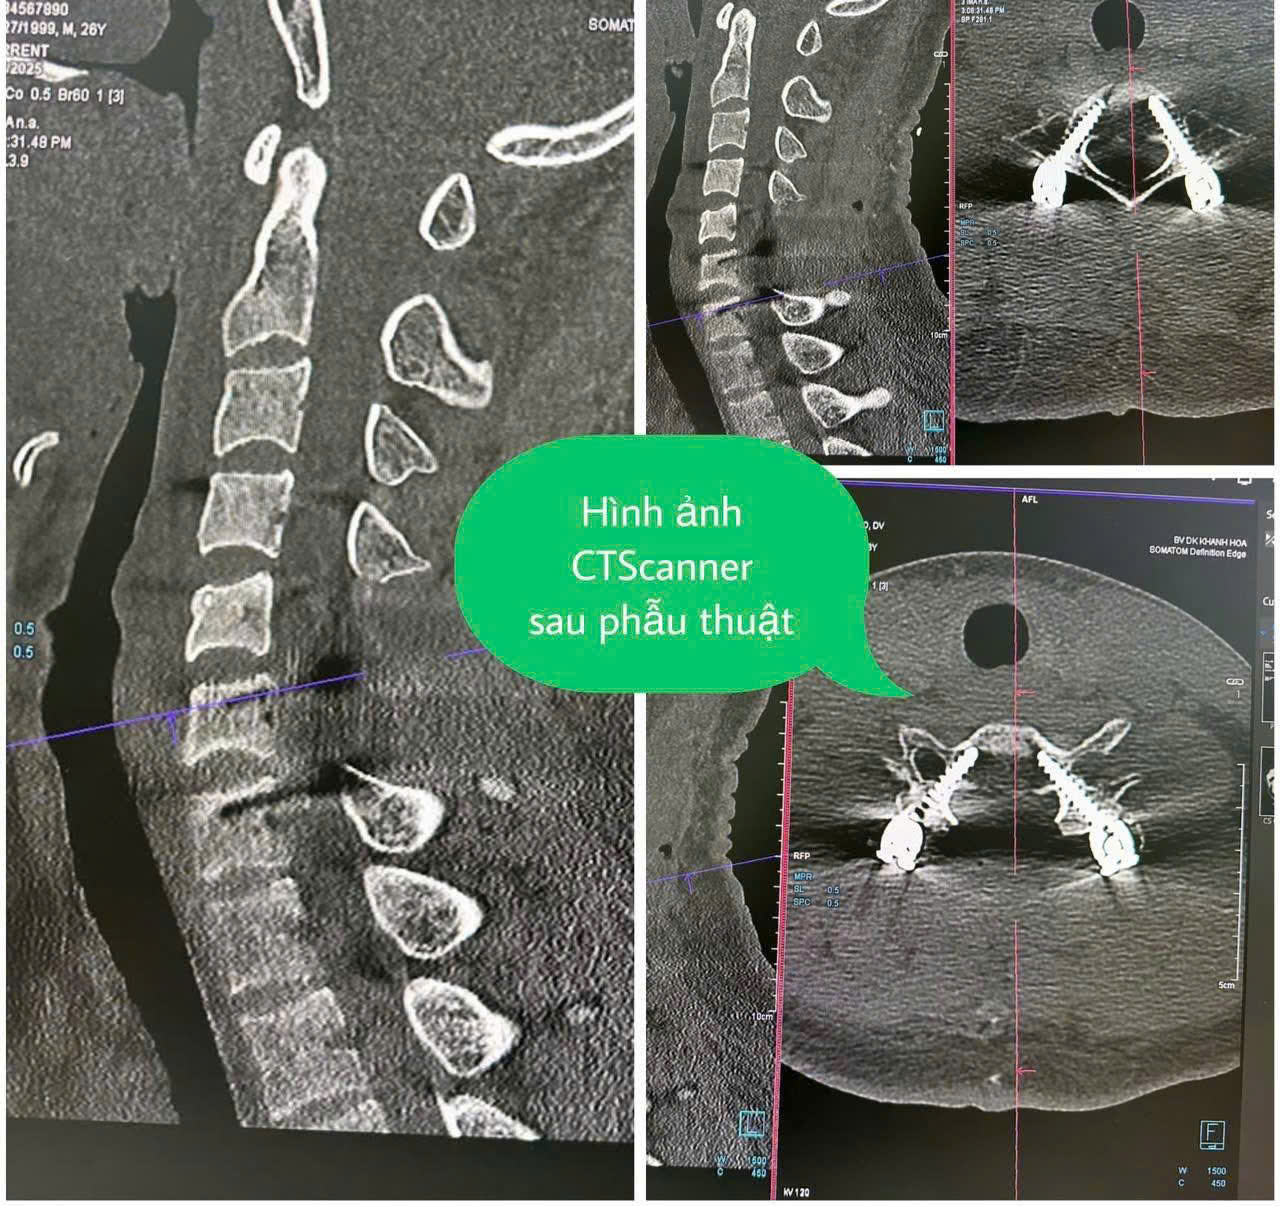

Bệnh nhân nhập viện trong tình trạng liệt tứ chi và bí tiểu cấp tính do bị chèn ép tủy, nguy cơ cao để lại di chứng nếu không điều trị kịp thời. Sau khi thăm khám và thực hiện các cận lâm sàng, bác sĩ xác định bệnh nhân bị gãy nhiều mảnh đốt sống cổ, tổn thương tủy. Với tình trạng nguy kịch của bệnh nhân, ê-kíp bác sĩ Khoa Ngoại cột sống và Khoa Phẫu thuật - Gây mê hồi sức đã tiến hành phẫu thuật cố định bằng vít chân cung cột sống cổ, giải phóng chèn ép tủy cho bệnh nhân. Sau 4 giờ phẫu thuật, ca mổ thành công. Kết quả kiểm tra bằng hình ảnh cho thấy, hệ thống cố định vững chắc, kết hợp xương chính xác từng vị trí. Bệnh nhân sau phẫu thuật hồi phục tốt, có lại cảm giác, đặc biệt người bệnh cử động được tứ chi.